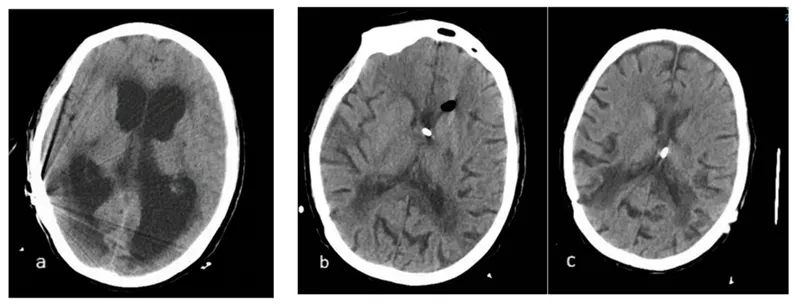

• The primary NPH treatment is the surgical implantation of a shunt, a device that drains excess cerebrospinal fluid from the brain to another body cavity.

• Early diagnosis is crucial because shunt surgery for NPH can significantly improve symptoms, especially gait problems, reversing many of the debilitating effects.